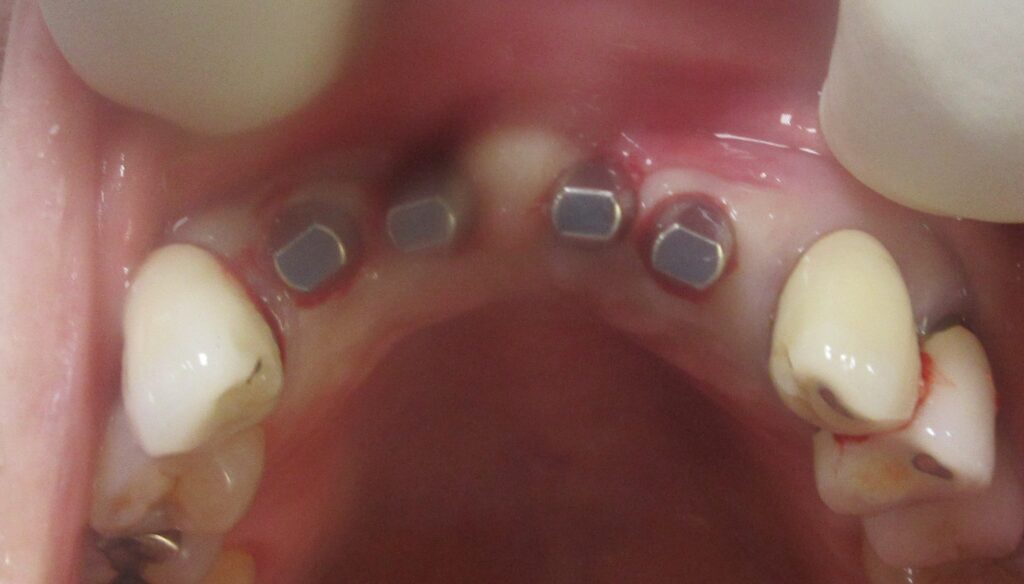

まずは左上1番目の歯茎から骨の部分までを穴開けパンチの要領で穴を開けていきます。

くりぬいた部分の歯肉を取り除き、次は骨に穴を開けていきます。

開けた穴に、専用道具を使ってネジを締めるように長さ2センチ程のインプラントを骨に埋め込んでいきます。

続けて他の歯も同じように植立していきます。

インプラントオペでは、複数本を植立する場合でも、当時進行はせず、1本ずつ同じ工程を繰り返して植立します。